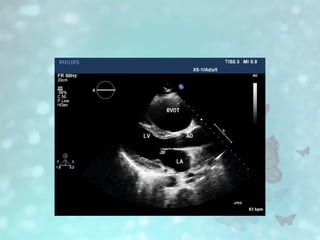

• Echocardiography

• Echocardiography has inconsistent sensitivity and specificity

for the diagnosis of ARVC and is not considered a primary

modality in the final diagnosis

• Supportive features include:

• Disproportionate enlargement of the basal right ventricle

• Secondary ("functional") tricuspid regurgitation

– associated with right ventricular dilatation and dysfunction

• Intensely echogenic moderator band

• Echocardiography • Echocardiographyhas inconsistent sensitivity and specificity for the diagnosis of ARVC and is not considered a primary modality in the final diagnosis • Supportive features include: • Disproportionate enlargement of the basal right ventricle • Secondary ("functional") tricuspid regurgitation – associated with right ventricular dilatation and dysfunction • Intensely echogenic moderator band